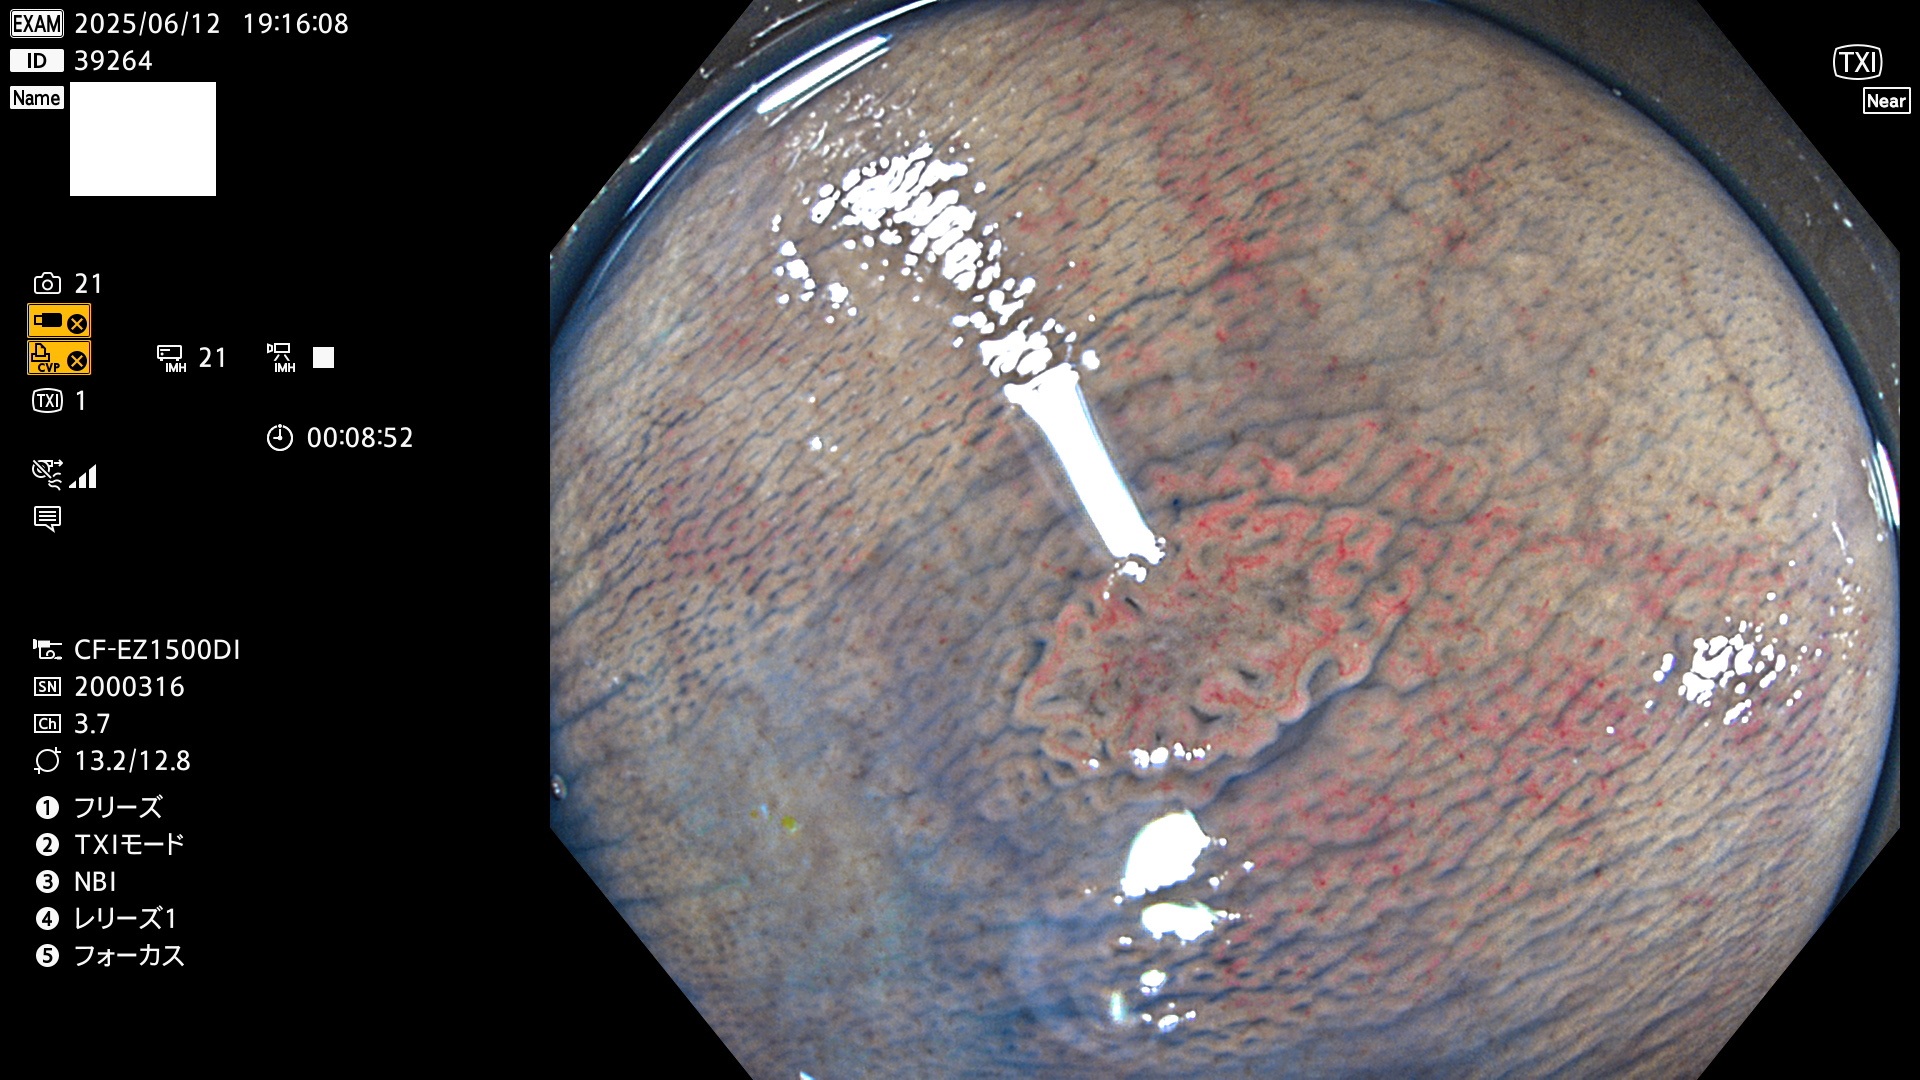

完全に平坦な物をUb、陥凹している物をUcと呼びます。Ubは認識が困難で、Ucはびらん(炎症)と紛らわしいために見落とされやすく、「内視鏡後・大腸癌」の原因になります。

抽出の対象期間 2025年6月12日〜6月15日の4日間(48件の検査)14個 (14/48=29%)